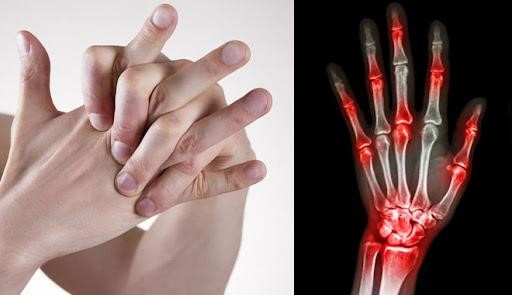

1. Bẻ tay, vặn lưng, cổ quá mức

Việc bẻ khớp ngón tay, vặn lưng, vặn cổ, các khớp hoạt động nhanh đột ngột và quá tầm vận động, dẫn đến việc phá hủy các cấu trúc sụn khớp và dây chằng xung quanh khớp nên rất có hại cho khớp. Đây chính là nguyên nhân khiến các khớp ngày càng to lên. Đồng thời, cũng có thể gây ra nhưng tổn thương như: bong gân, giãn dây chằng, trật khớp, làm sụn khớp nhanh bào mòn và đẩy nhanh quá trình lão hóa.

Nếu không bỏ thói quen này, khớp sẽ bị thoái hóa, biến dạng khớp, to khớp ở vùng các ngón tay hay rách dây chằng, thoát vị đĩa đệm cột sống cổ, cột sống thắt lưng, thoát vị nhân đĩa đệm gây chèn ép rễ thần kinh...